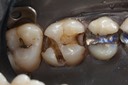

Mark Chun #17 prep